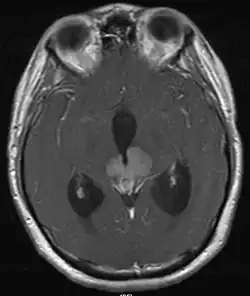

На основании этих проявлений, врач проводит исследования крови, компьютерную томограмму, МРТ, эхо-энцефалографию.

Герминома, среди всех опухолей мозга, занимает лишь 2 %, диагностируется в возрасте 10-12 лет, реже к 20 годам. Этому заболеванию подвержены чаще мужчины[5]. При диагностике данного заболевания, характерны симптомы гипофизарно-гипоталамической недостаточности (замедление роста, гипопитуитаризм, несахарный диабет). При исследовании с помощью рентгена данная опухоль может не определяться, особенно на ранних стадиях. При лабораторных исследованиях часто тестируются сывороточные и спинномозговые опухолевые маркеры альфа-фетопротеина (АФП) и бета-ХГЧ. Истинные герминомы не связаны с этими маркерами. Нергерминоматозные опухоли могут быть связаны с повышенными маркерами, такими как AFP, с эмбриональными клеточными карциномами и незрелыми тератомами и бета-ХГЧ, которые встречаются при хориокарциномах. У 1 до 15 % гермином может быть получен низкий уровень бета-ХГЧ. HCG-секретирующие герминомы могут быть более агрессивными, чем несекретирующие.

Локализация при расположении в головном мозге :

- шишковидное тело;

- перекрест зрительных нервов;

- гипоталамус;

- третий желудочек;

- гипофиз;

- область основания.